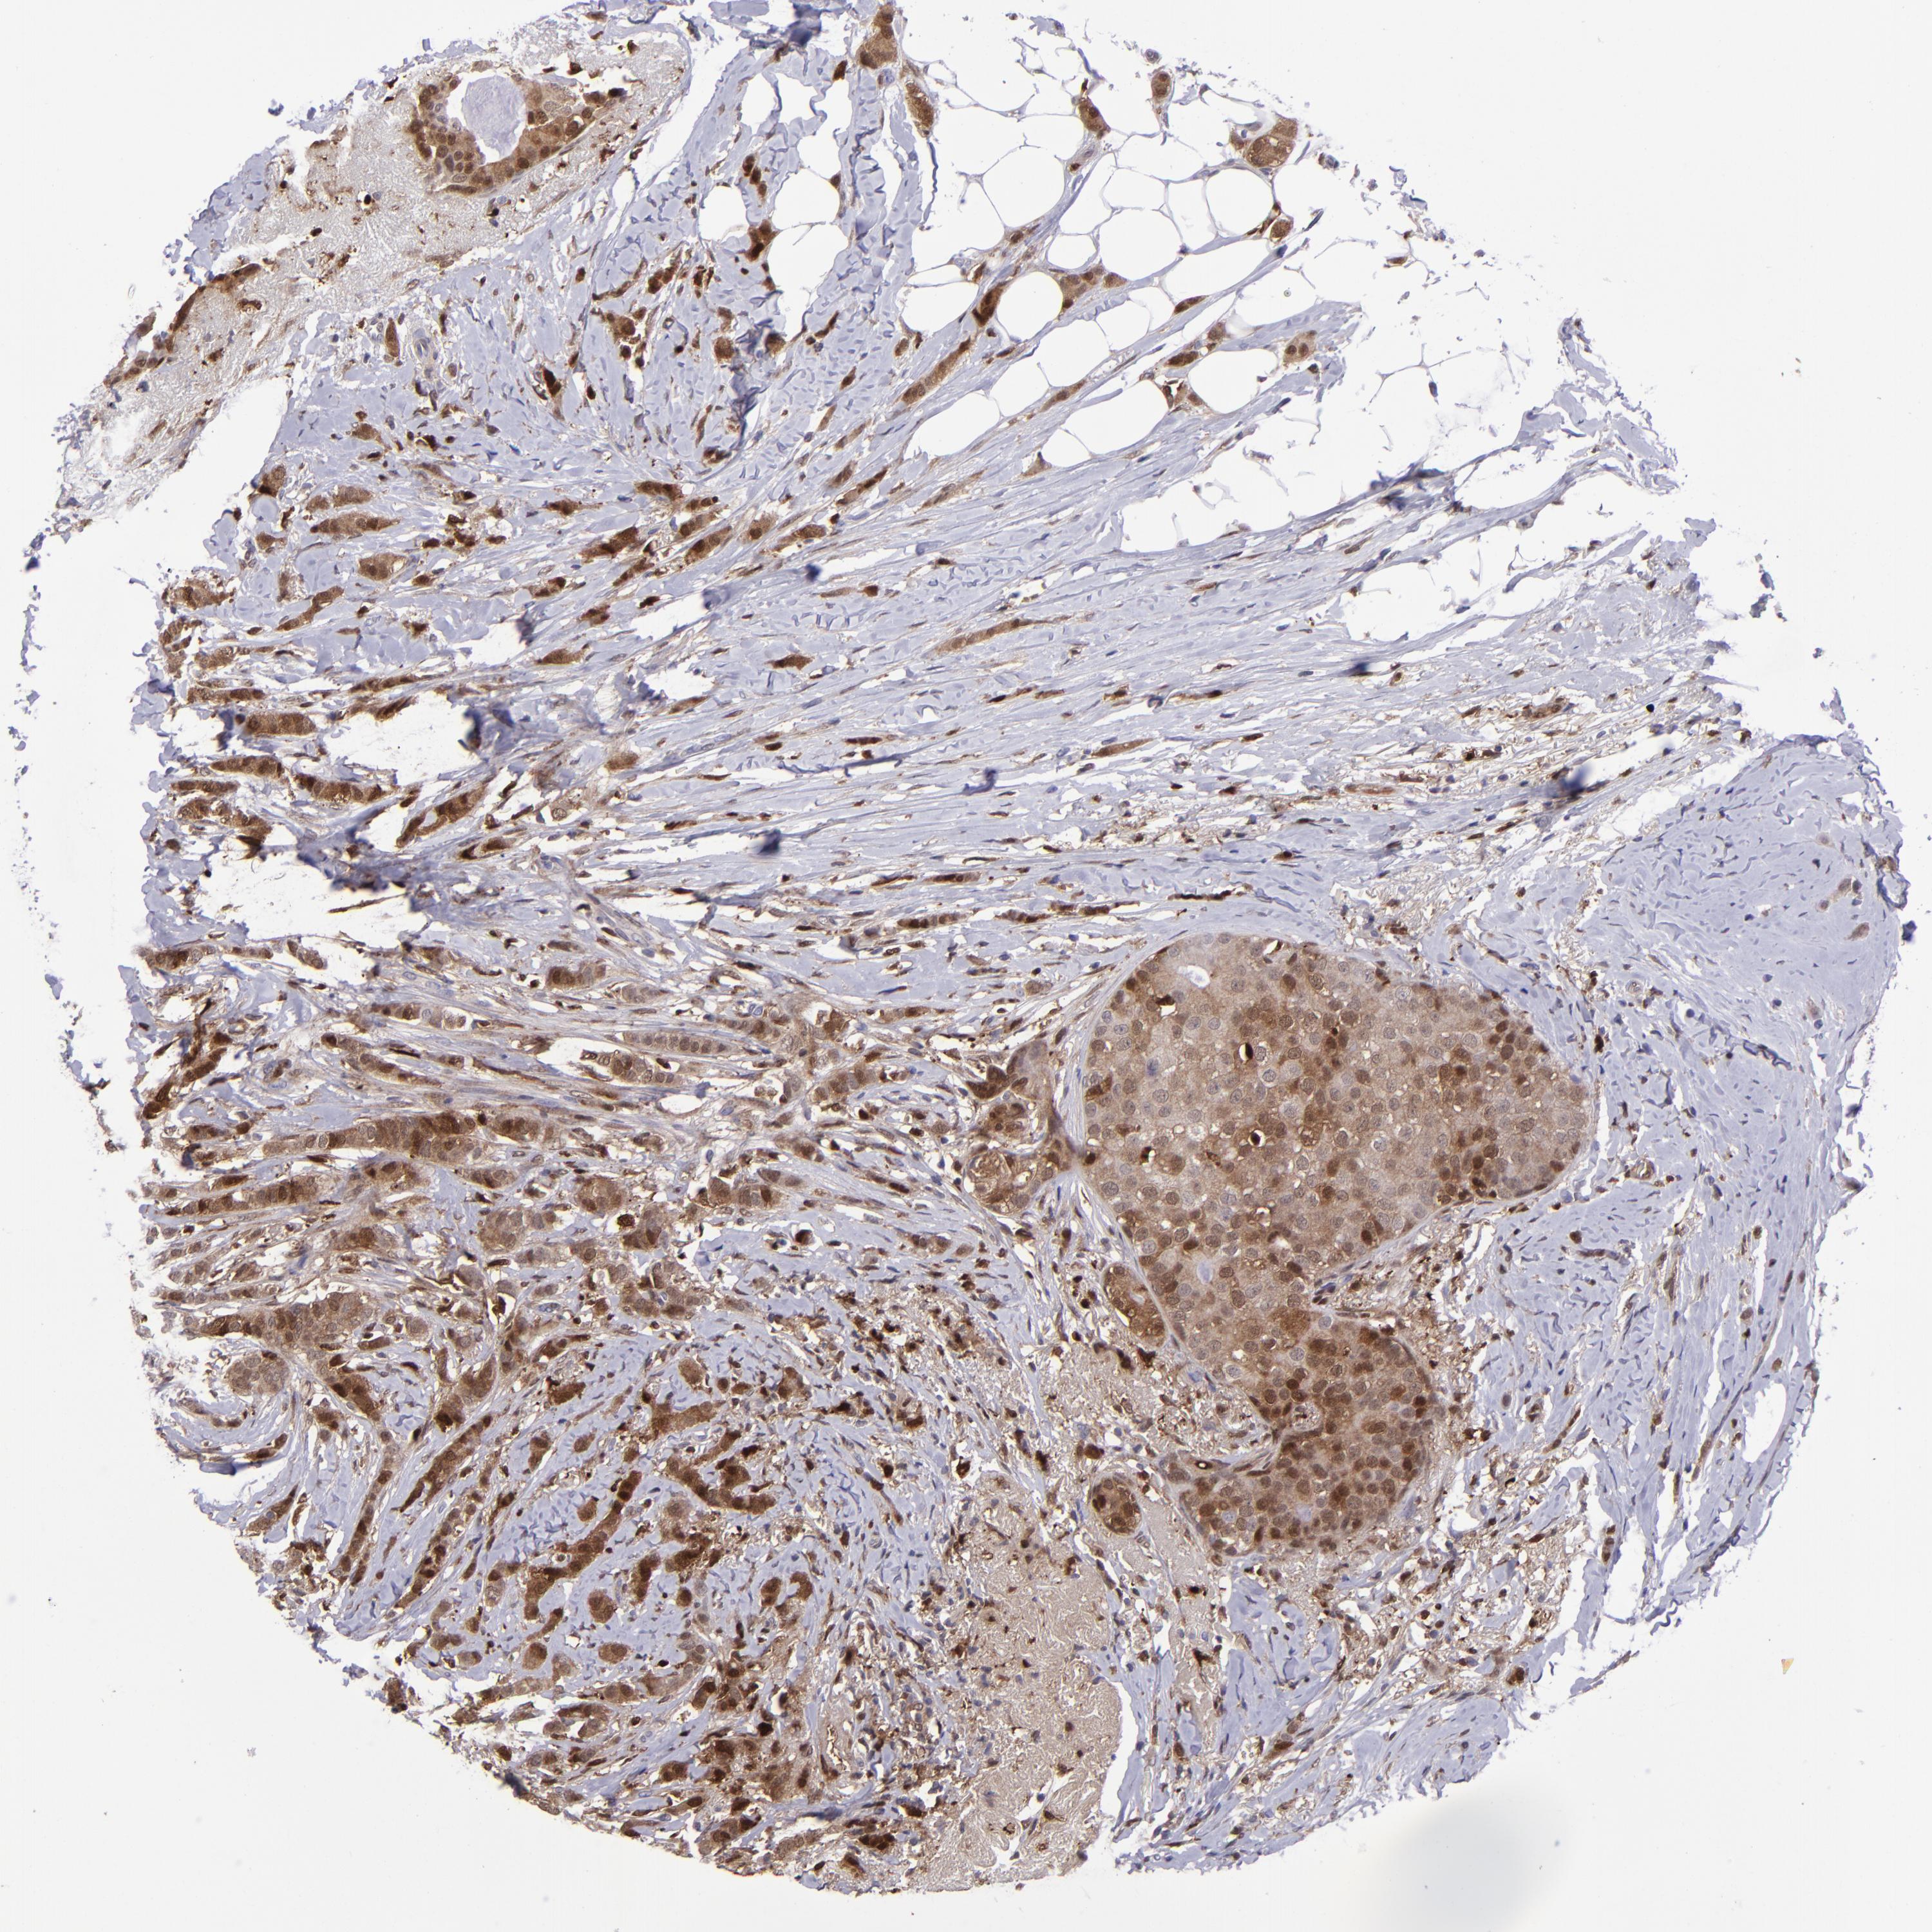

BRCA TCGA BRCA VALIDATION PROTEIN EXPRESSION

ANTIBODIES

AND

VALIDATION